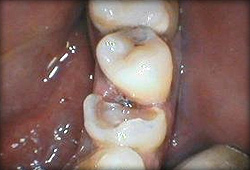

Or maybe composite restoration with a fiberglass reinforcement